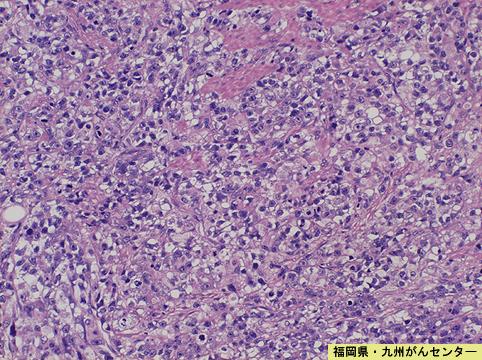

症例提示(所在地,施設名等): 福岡県・ 九州がんセンター

画像ID:4853

[ 画像ID:4853 ]

疾患(病理主体)の分類悪性上皮性腫瘍/腺癌

部位(臓器別)胃(部位)/体部

検査方法ミクロ

腫瘍の肉眼分類5型(分類不能)/

病変の最大径(ミリ)40以上

腫瘍の深達度ss(a1)